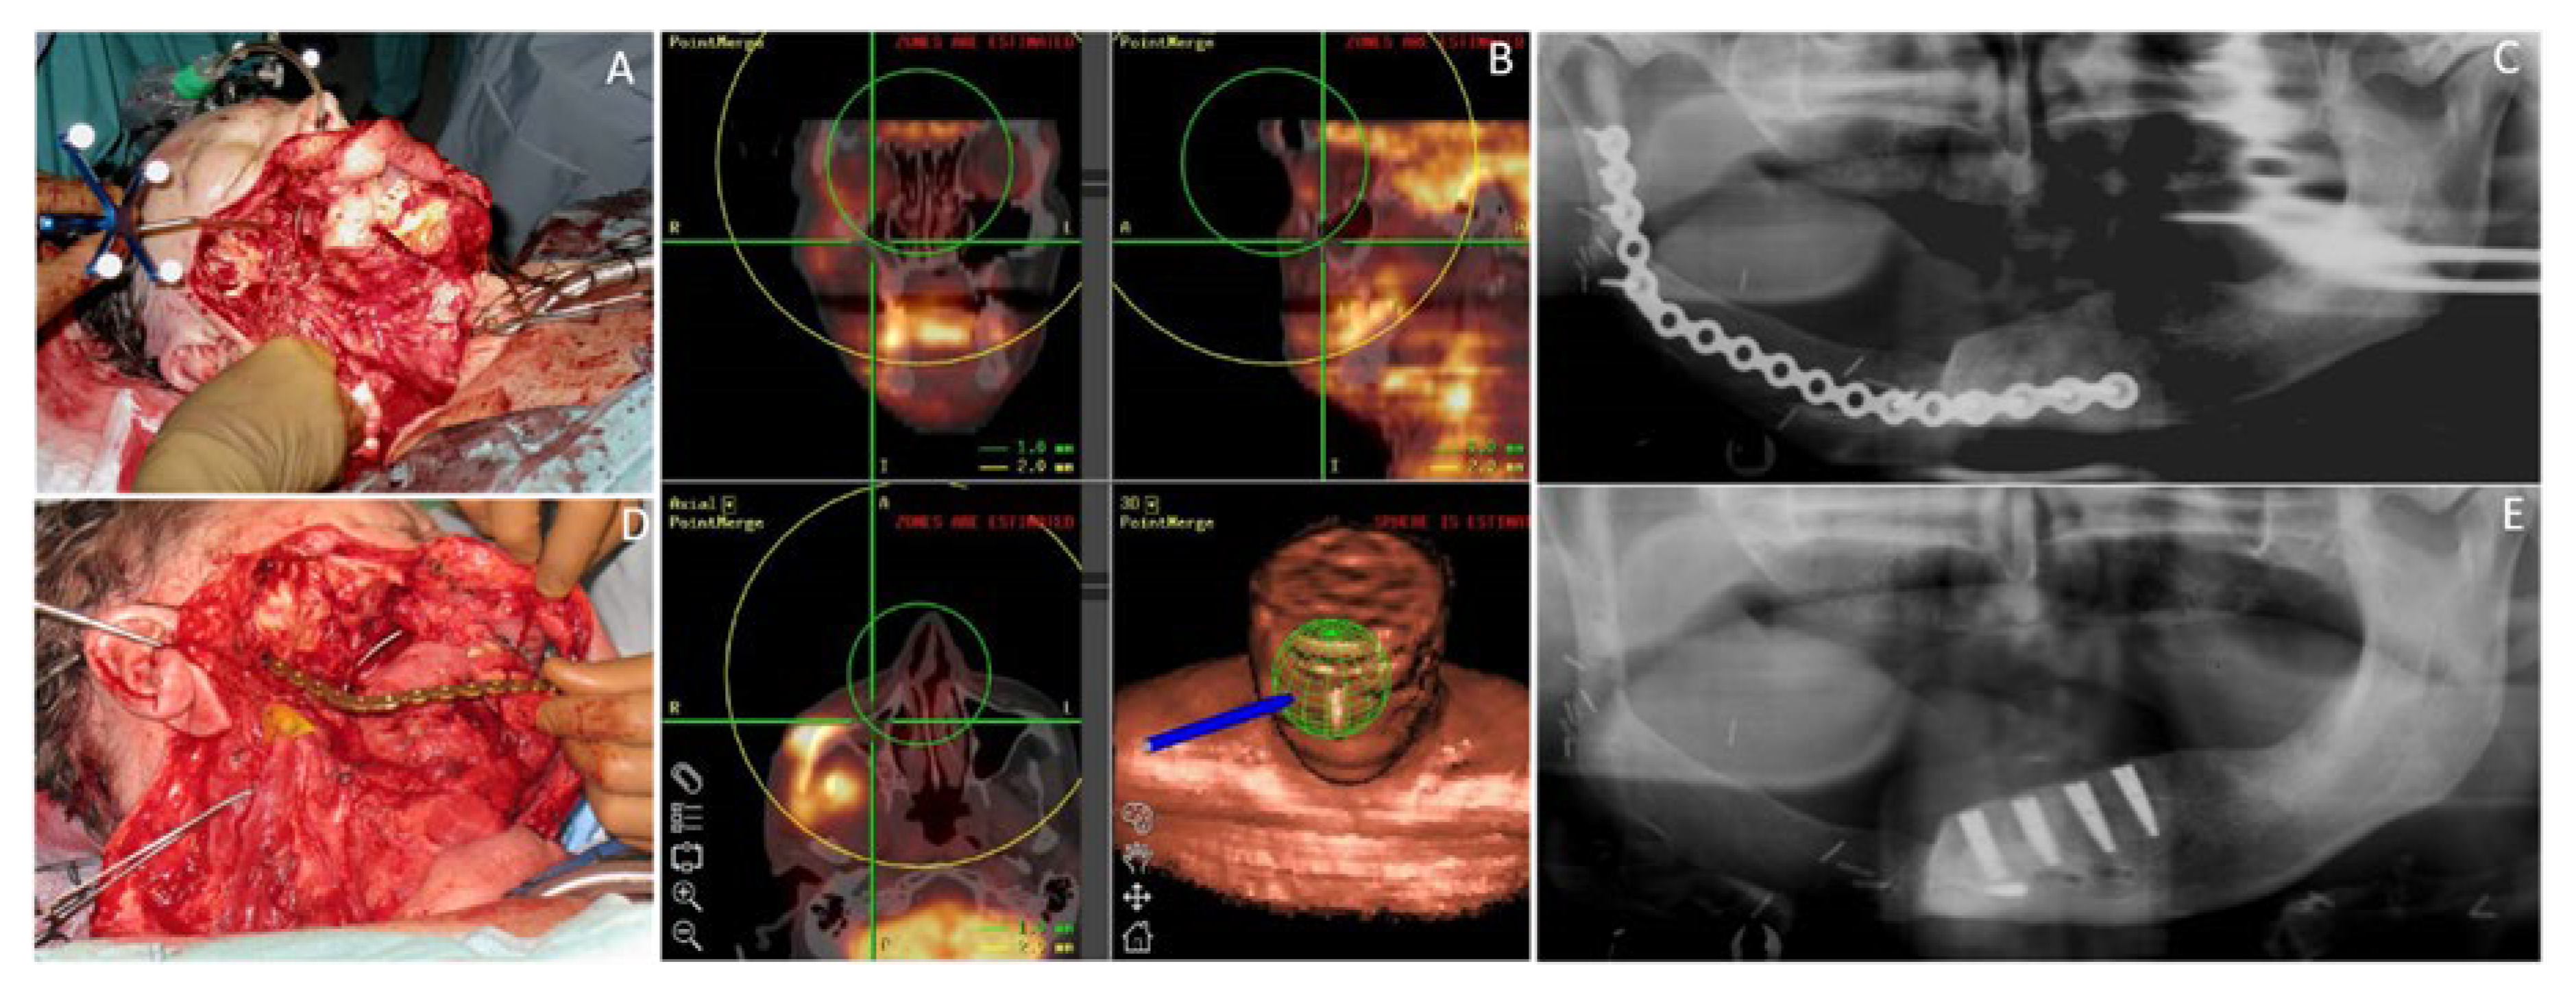

Figure 5.

Fifty-seven-year-old male patient with a squamous cell carcinoma of the oral cavity (OCSCC) affecting the mandible reconstructed with the subscapular system free flap. (A) Intraoperative view of a large defect after navigated tumor resection; (B) Depiction of the 3D-navigation system based on PET/CT image-fusion, used perioperatively; (C) Postoperative dental panoramic radiograph after composite mandible reconstruction with the SFF. (D) Intraoperative view after insertion and fixation of the bony transplant of SFF reconstructing the mandible; (E) Postoperative dental panoramic radiograph after insertion of the dental implants.